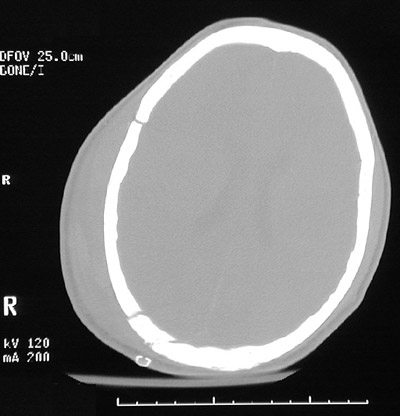

| This head CT scan in "bone window" demonstrates a skull fractures on the right with diastasis of the sutures. However, this is not a depressed skull fracture. There is marked overlying soft tissue swelling in the scalp, and a small laceration has been closed with staples. In the view below following craniotomy for removal of an epidural hematoma, the swelling has diminished and the posterior fracture has been stabilized with a short metal plate. |